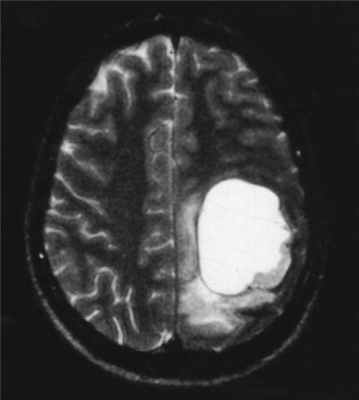

МРТ головного мозга. Анапластическая астроцитома. Корональные Т2-зависимая МРТ и Т1-зависимая МРТ с контрастированием.